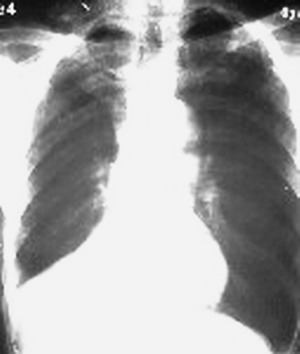

1:右侧结核性胸膜炎,胸腔积液;

2:不排除右肺癌。

右肺下叶支气管阻塞,右下叶不张,考虑中心型肺癌伴下叶不张

先考虑:右下肺中心型肺癌伴下叶肺不张、胸腔积液

右肺下叶支气管闭塞,中间段支气管狭窄,下叶不张,胸腔及叶间积液.中心型肺癌伴下叶肺不张.胸腔和叶间积液.

右肺下野后部均匀低密度影,边缘锐利,前缘外突(不支持肺不张),纵隔内未见明显肿大淋巴结,右下肺门结构显示欠清,临床资料太过简单,考虑右侧后胸部包裹性积液。其他待排。建议密切结合临床其他检查。